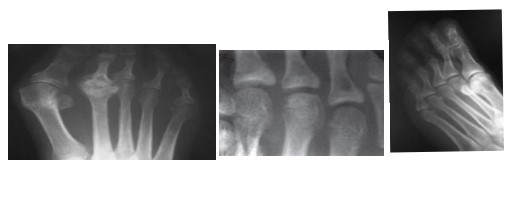

Iselin

Epifisite da base do 5º mtt por tração pelo fibular curto

DD: Os Vesalianum (Sesamoide do fibular curto)

Rx: fragmento inferolateral (só se vê no oblíquo), bordas irregulares

Complicação: PSA

Freiberg

Osteocondrite da cabeça dos MTT

2º mtt 70%

Dor em atividades, limitação da adm

Sinal de depressão de Freiberg = Achatamento da cabeça do mtt

Radiolucencia

Esclerose marginal